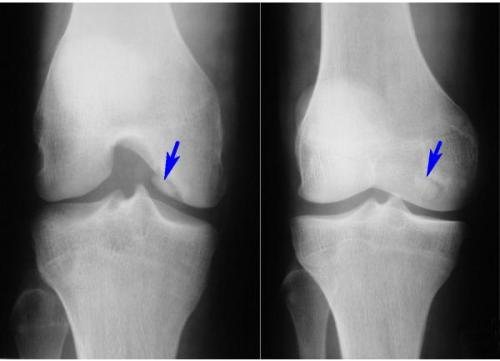

На рентгенограмме чаще всего отмечается один осколок, хотя в некоторых случаях их может быть до 7, хотя такое встречается очень редко.

Очень часто такое состояние принимается за какое-то другое заболевание, особенно в случае, когда боли в колене появились после травмы. Так, например, некоторые списывают это на сильный ушиб, растяжение связок и другие мелочи. Но такая невнимательность нередко приводит довольно тяжёлым последствиям. Поэтому при обследовании очень важно не только сделать рентгенологическое исследование, но и тщательно собрать анамнез жизни пациента и предшествующей болям травмы. Причём проявляться данная проблема может и в локтевом суставе.

Диагностика суставной мыши обычно включает физический осмотр, а также визуализирующие методы, такие как рентгенография, магнитно-резонансная томография (МРТ) или ультразвуковое исследование. Эти методы помогают выявить наличие свободных фрагментов в суставной полости и оценить состояние окружающих тканей.